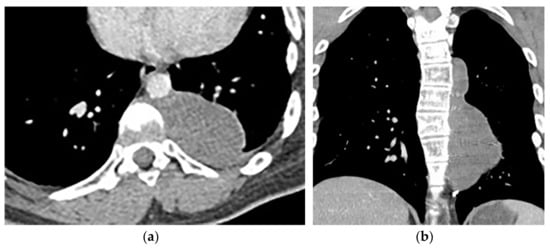

8.2. Tuberculosis Spondylodiskitis

Tuberculosis spondylodiskitis has a more gradual and chronic clinical course, which leads to multi-level involvement and paravertebral cold abscess formation with well-circumscribed thin wall. Subligamentous spread of infection to adjacent vertebral levels, relative preservation of intervertebral disk, and kyphotic angulation (gibbous deformity) are other imaging findings. CT scan is more sensitive in delineating calcification within paravertebral cold abscess, end plate erosion, and bony fragment visualization (Figure 13) [39,42].

Figure 13.

A 65-year-old man with fever, weight loss, and night sweeting. The non-contrast-enhanced CT (bone window) in axial plane (a) shows paraspinal soft tissue mass with erosion of right lateral aspect of adjacent vertebral body. Sagittal T2W image of another patient with the same pathology (b) shows hypersignal intensity within T8-T9 vertebral bodies with also intervertebral disc destruction and narrowing of spinal canal pushing the spinal cord posteriorly. Axial T1WFS + C (c) identified the enhancing paraspinal mass with peripheral rim enhancement (arrow) in its left posteromedial side, which is suggestive of abscess formation. Culture of aspirated pus under guide of CT was compatible with tuberculosis infection.